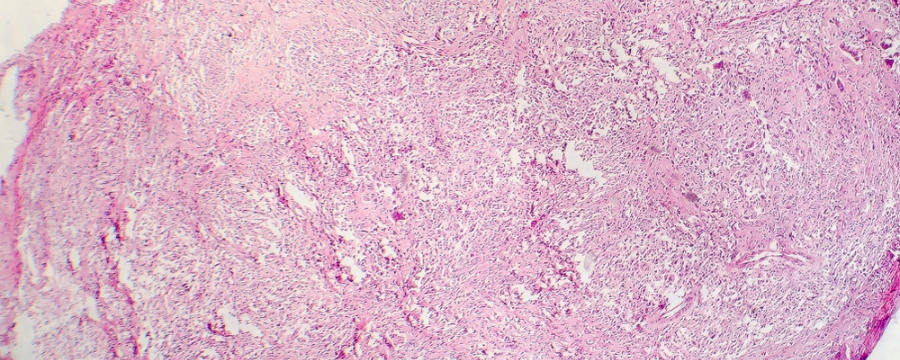

donovanosis

¿Qué es la donovanosis?

La donovanosis, también conocida como granuloma inguinal, es una enfermedad de transmisión sexual (ETS) poco común. Sin embargo, conviene conocerla para identificar sus síntomas con el tiempo suficiente para poder diagnosticarla sin demora y ponerle solución. La causante de esta enfermedad es una bacteria que afecta al área ano-genital.